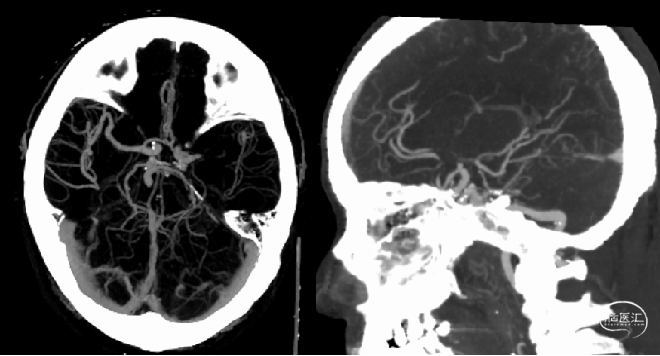

查体情况:NIHSS 评分22分;ASPECT评分10分。

CTP:

脑血管造影情况:右侧股动脉穿刺,穿刺至发病时间5.33小时。行全脑血管造影示:左侧大脑中动脉急性闭塞,左侧大脑前动脉、大脑后动脉通过脑膜支代偿左侧大脑中动脉供血区,并逆流至M1远端。

术前正位

术前侧位